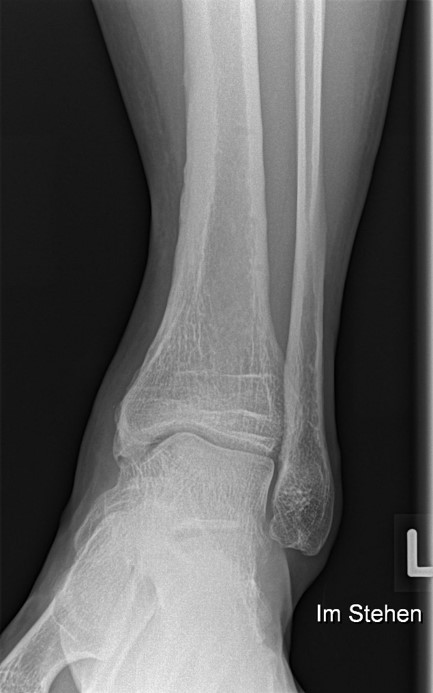

Die Standard Röntgendiagnostik des Sprunggelenks umfasst Bilder in anteriorposterioren (a.p.) und im seitlichen Strahlengang 6. Für die exakte Abbildung des Innenknöchels müssen beide Malleolen parallel zur Röntgenplatte zu liegen kommen. Je nach Torsion der Tibia macht dies eine Innenrotation des Fußes zwischen 10° und 30° erforderlich (Abb. 3).

Manchmal sind mediale Malleolarfrakturen nur in einer der Aufnahmen in ihrem Ausmaß erkennbar. Keine Rolle spielt die gehaltene Aufnahme beim Kind, insbesondere bei der akuten Verletzung. In seltenen Fällen hat dieses Verfahren bei Verdacht auf eine chronische Instabilität eine Berechtigung.